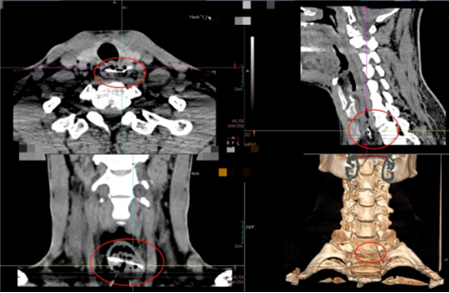

5岁女孩被猪骨卡喉半小时。

43岁大叔4小时前被鸡骨卡咽喉,且刺穿食管,引起食管周围及上纵膈内较多游离气体。